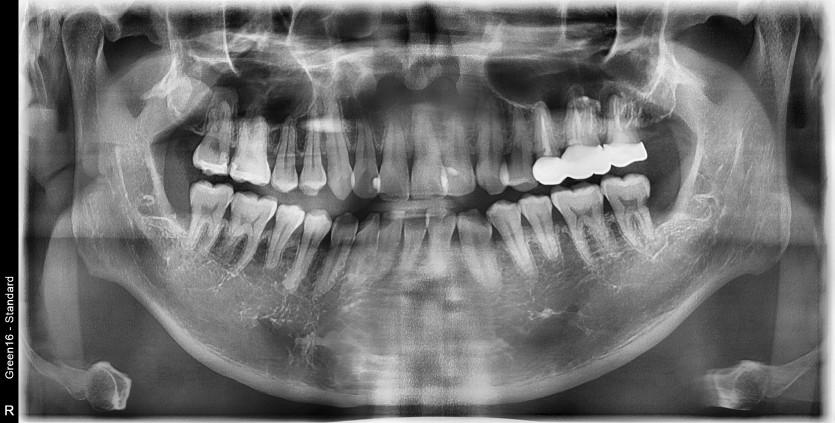

#28,38,48 사랑니 발치

구강 외과 전문의가 당일 발치했습니다.